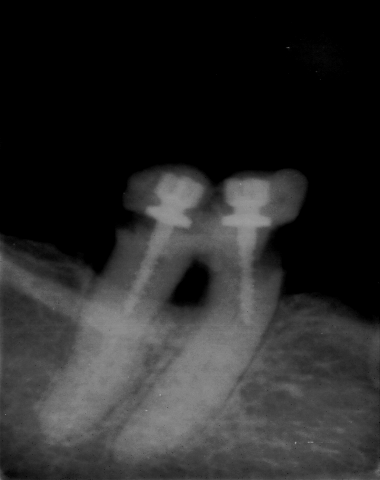

enfin le document tant attendu--------------------dans le compagnonnage on appelle cela un chef d'oeuvre( "d'architecture" bien sur)--ceci prouve que l'on peut se passer d'obturation canalaire,alors à quoi cela sert une nouvelle convention ?---un petit truc pour les non initiés:avec un thrombone c'est possible aussi ---un autre truc vous séparez les 2 racines et vous avez 2 sc33 , qui dis mieux ? Allez je lance un grand concours de photos dans le meme style ---les dentistes conseil peuvent y participer, of course

belle reconstitution et a priori très solide puisque c'est la dernière dent de l'arcade à être en place

En tout cas, peterpan, ta photo est bien passée, youpee, et tu as gardé ton flegme devant une certaine forme de bizuthage typiquement eugenolienne!!!. Bon la dent.... sans retraitement et avec le petit liseré vertical qu'on voit entre les deux racines, et la limite osseuse qui a connu des jours bien meilleurs , je pense que la photo sur eugenol aura une plus grande longévité.

Et, mode sérieux on; tu as le droit de coter une hémisection et un retraitement pour une même dent, mais pas deux sc33, interdit, forbidden zone!!!

adhoc je te remercie pour tout ce que tu fais pour moi ,par contre je ne suis pas tout a fait d'accord avec toi sur les 2 sc33, je pense que cela est tout a fait possible . Cela ressemble a une 46 au départ,imagine un instant, après la séparation de racine, une migration distale de 44 et 45 ,cela s'est déja vu meme sans ortho. Je te le dis c'est imparable. j'attends l'avis des ------"spécialistes"----Jespère n'avoir vexé personne ce coup ci .Bien le bonjour de clochette : très contente de l'effet que vous faites sur peter----------Tiens en vla une autre (de radio)----surlécutant , comme disais l'autre---là malheureusement séparation de racine impossible,par contre, encore une fois économie de bio ,mais petit "rattrapage" par extraction ,attendons le joli mois de mai: dc16 je crois avec la nouvelle convention, c'est fou ce qu'on peut prolonger avec les antibio......